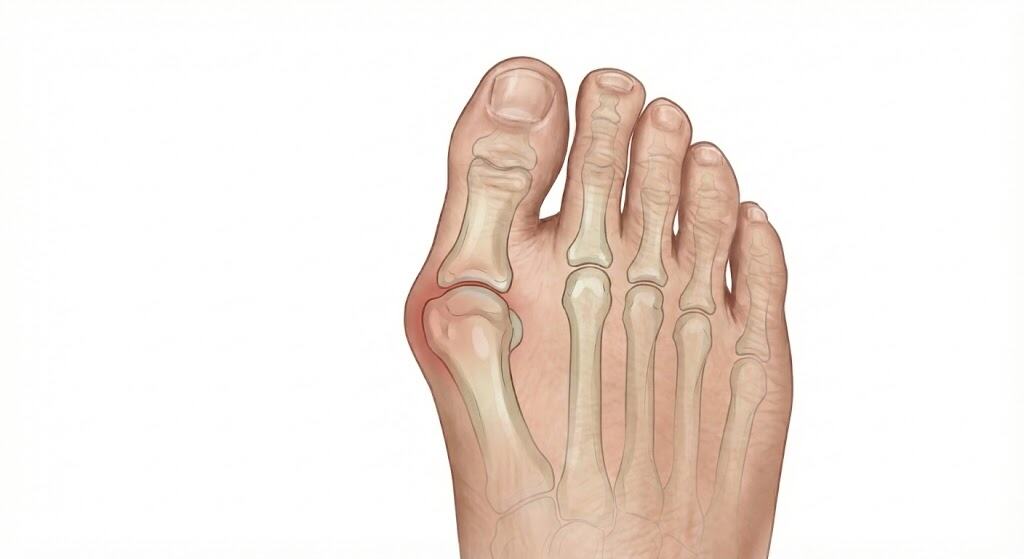

הלוקס ואלגוס (Hallux Valgus) אינו סתם "גוש" שגדל על הרגל, אלא כשל מבני מתקדם של קדמת כף הרגל. כדי להבין את הבעיה, צריך לדמיין את המפרק כציר דלת שיצא ממקומו, ולא כעצם שגדלה פתאום.

העיוות הוא תלת-מימדי ופרוגרסיבי (מחמיר עם הזמן), והוא מתרחש בשני מישורים במקביל – העצם והרקמה הרכה:

במצב תקין, עצם המסרק (Metatarsal) והבוהן (Phalanx) יוצרות קו ישר. בהלוקס ואלגוס, האיזון הזה מופר ונוצרת תנועת מספריים:

- נדידת עצם המסרק פנימה (Metatarsus Primus Varus): האירוע הראשוני הוא לרוב תזוזה של עצם המסרק הראשונה (העצם הארוכה בבסיס הבוהן) לכיוון המדיאלי (לכיוון הרגל השנייה). תנועה זו גורמת ל"פתיחת מניפה" של עצמות המסרק, מה שמרחיב את רוחב כף הרגל הקדמית (Splay foot). כתוצאה מכך, ראש העצם נחשף ובולט החוצה.

- בריחת הבוהן החוצה (Hallux Valgus): כפיצוי או כתגובה לתזוזת המסרק, הגליל המקורב של הבוהן (האצבע עצמה) נמשך לכיוון הנגדי – הצידה, לעבר האצבעות הקטנות.

- התוצאה – תת-פריקה (Subluxation): המשטח המפרקי של הבוהן כבר לא יושב "מול" המשטח המפרקי של המסרק. המפרק עובד בצורה עקומה, מה שיוצר שחיקת סחוס מואצת (Arthritis) וכאב עמוק בתוך המפרק.

4. ה"בליטה" (The Bunion)

מה שאנו רואים בעין כ"עצם בולטת" מורכב משלושה דברים:

עיבוי עור: יצירת עור קשה (Callus) על הבליטה כתגובת הגנה.

ראש עצם המסרק: שפשוט נחשף החוצה עקב התזוזה.

בורסיטיס (Bursitis): שק נוזלים (בורסה) שנוצר בין העצם לעור כדי להגן על האזור. בגלל החיכוך בנעל, השק הזה הופך דלקתי, נפוח, אדום ורגיש מאוד למגע.